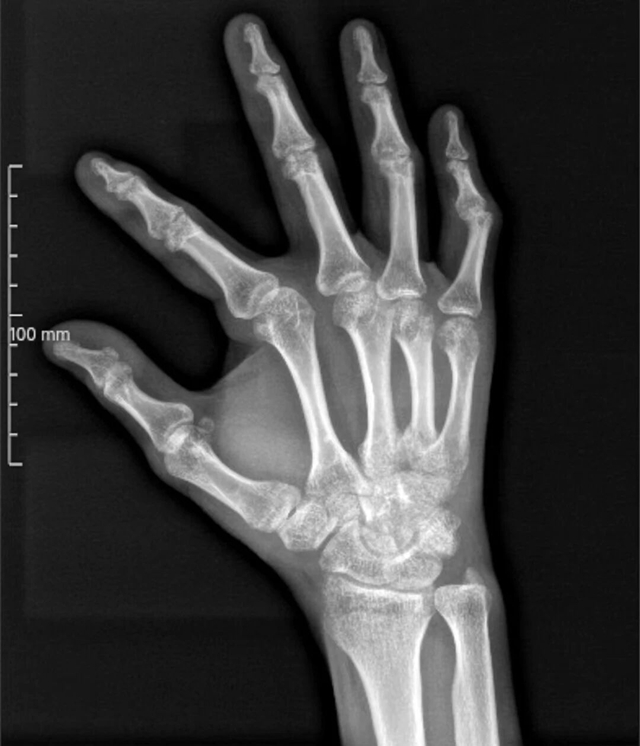

经过拍片检查,医生给出的结论一致:右手骨折伴关节脱位,需要手术治疗。可这个结果让小杨犯了难,他今年才29岁,特别在意形象,生怕手术会在手上留下疤痕,影响美观,并且数万元的手术费可是他好几个月的工资,无论如何都不愿意接受手术。

江锋医生接诊后,仔细查看了他的检查片子,又认真检查了他的右手情况,结合小杨“怕留疤、不愿手术、节约费用”的诉求,经过慎重评估后,决定为他采用中医正骨手法复位治疗。

确定治疗方案后,江锋医生会同科室的王念武医生立即制定了详细的复位计划。手法复位看似简单,实则非常考验医生的经验和技巧,每一个动作都要精准到位,既要将错位的骨折端复位,又要避免对周围组织造成二次损伤。

复位过程中,江锋医生一边耐心安抚小杨的情绪,缓解他的紧张和疼痛,一边凭借娴熟的手法,调整骨折部位。在王念武医生的默契配合下,短短1分钟,“对抗牵引、擒拿扶正、端顶提按”原本错位的骨折和关节脱位就被成功复位,小杨擦着额头的汗水感叹到:“天哪医生,我都听到骨折咔嚓复位的声音了,手指也能活动了”。

复位成功后,江锋医生立即为小杨进行了骨折部位中药外敷,小夹板固定处理,并反复叮嘱他注意事项,告知他后续要定期复诊,按时进行康复锻炼,才能更好地恢复。